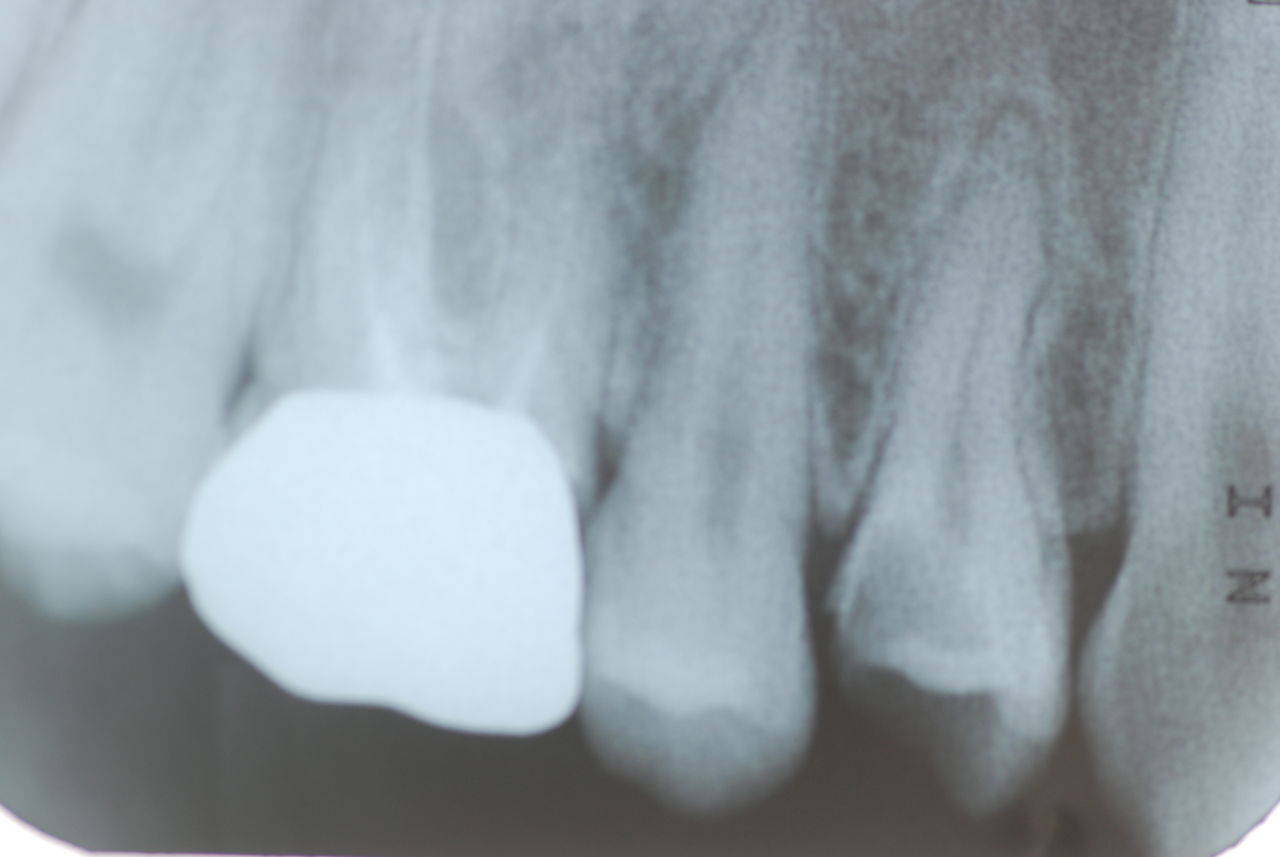

14年歯前、歯の神経が腐り、神経を除去したまま来なくなった現在大学生の女性

歯周病になっていましたが、少し色が黄色くなっているだけで比較的綺麗な歯の状態です。

平成9年来院神経を取り、同時に歯周病の話をしてそのまま来なくなっていたかたですが、たまたま一部欠けてきました。それで来院。

平成24年一部欠けて来院

15年前と同じように詰めて終了。磨き方はまあまあでした。でも問題少ないでしょう。![ea7f9628-s[1]](https://livedoor.blogimg.jp/netdental/imgs/c/2/c2ef91be.jpg)